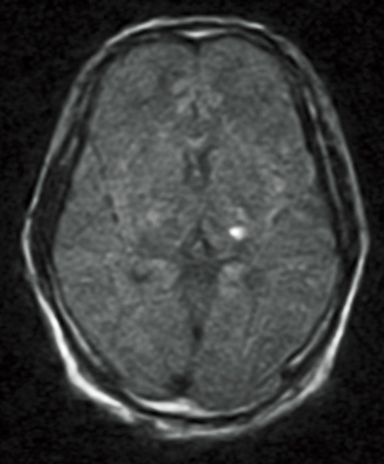

FLAIR

DWI

ADC map